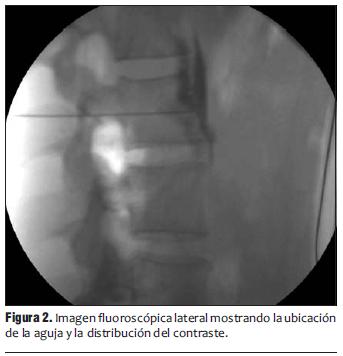

Se realizó un acceso lateral bajo fluoroscopía con enfoque oblicuo hasta lograr que el cuerpo vertebral cubriera la apófisis transversa, y se orientó la dirección de la aguja hasta tomar contacto con el borde anterolateral de los cuerpos de las vértebras lumbares L2, L3 y L4 (figura 1).

Se confirmó la posición de la punta de la aguja en el borde anterior del cuerpo vertebral con visión lateral, y su ubicación a nivel del pedículo en la línea facetaría en visión postero-anterior.